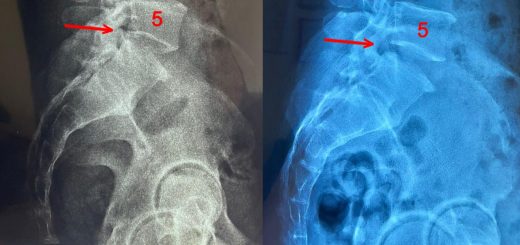

Reduced Hunching and Increment of 2cm Height